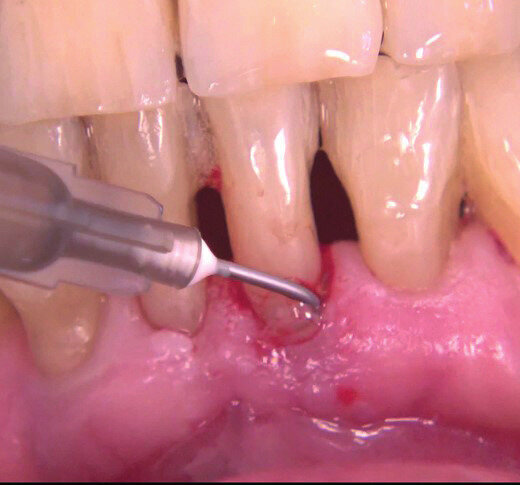

Il paziente di 71 anni con parodontite stadio III grado b presenta una tasca di 9 mm distale e vestibolare su 31 residua dopo trattamento causale (Figg. 6a, 6b). Il paziente presenta una buona igiene orale e aveva manifestato fastidio nella zona stessa. Le tasche presenti vengono ritrattate con u.s e curette mini-gracey e applicazione di Ozosan Gel per 8 min, lavaggio, nuova applicazione per 2 min e lavaggio con fisiologica (Fig. 7). A 3 settimane la zona si presenta con assenza di tasche patologiche (Fig. 8). Il paziente riferisce nessun disturbo in seguito al trattamento subito.

Fig. 7 - Applicazione di Ozosan.